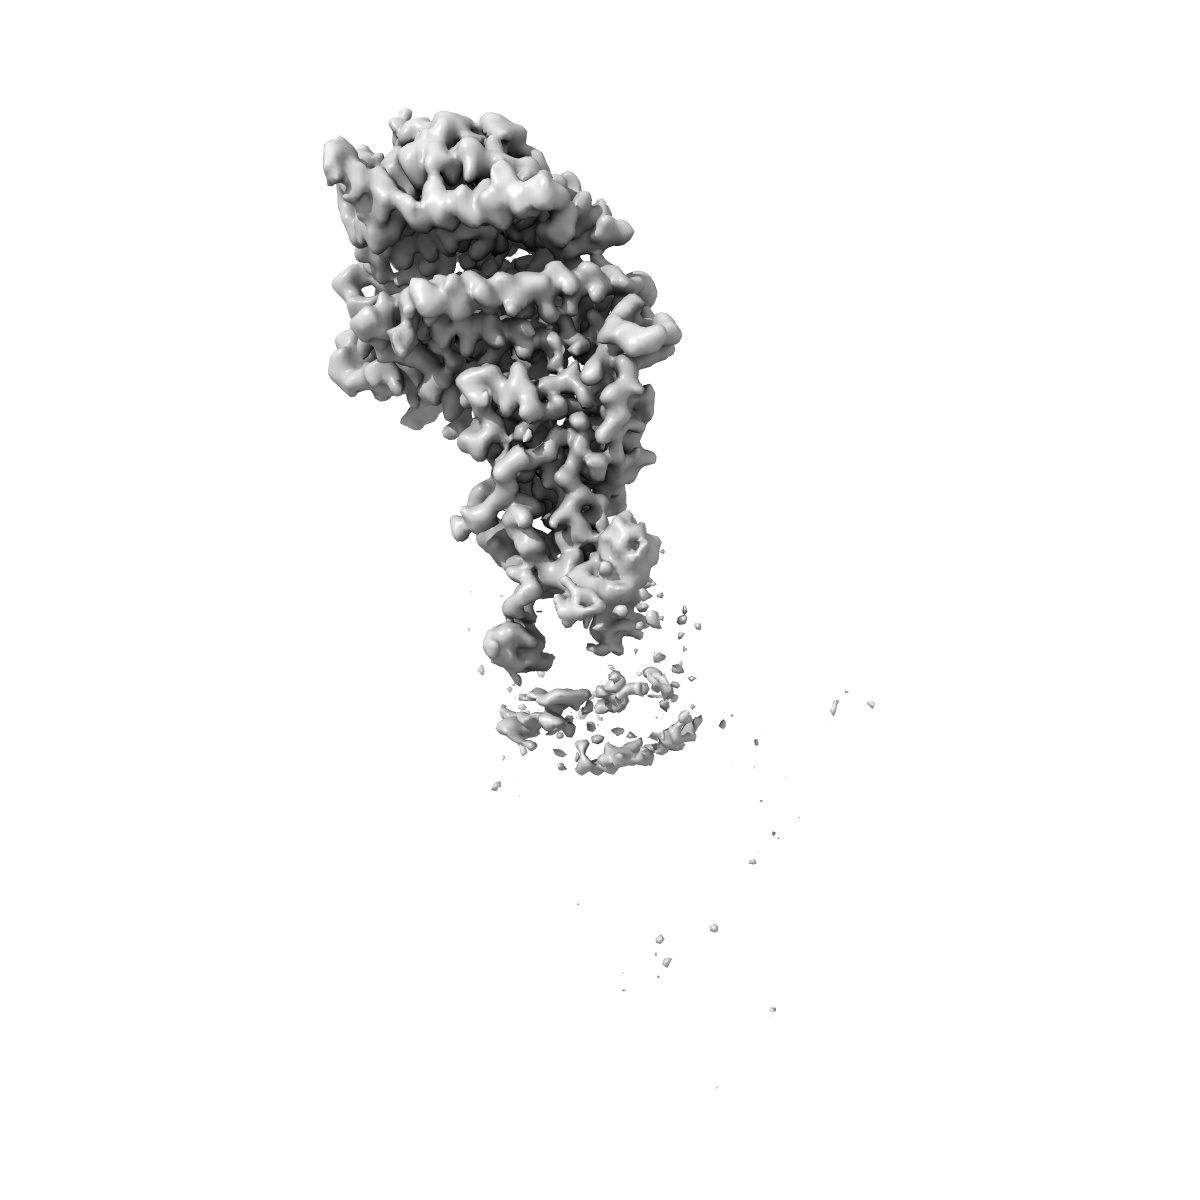

Cryo-EM structure of SARS-CoV-2 Alpha (B.1.1.7) spike protein in complex with human ACE2 (focused refinement of RBD and ACE2)

Single-particle3.04 Å

Sample: SARS-CoV-2 Alpha (B.1.1.7) spike protein in complex with human ACE2